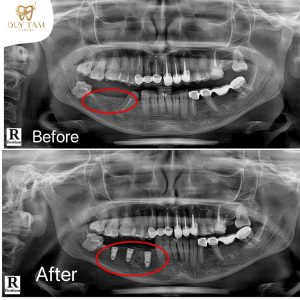

✔ Thiết bị chẩn đoán hiện đại (CT 3D, phần mềm phân tích Implant)

Giúp bác sĩ đánh giá mật độ xương và xác định vị trí đặt trụ chính xác.